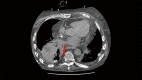

Though rare, pulmonary vascular complications after lung transplantation carry high morbidity and mortality. Knowledge of the normal and abnormal appearance of lung transplant vasculature is essential for timely and appropriate diagnosis and management of complications. Appropriate selection of surgical and endovascular treatments depend on the availability of expertise and requires a multidisciplinary approach to ensure the best outcomes.